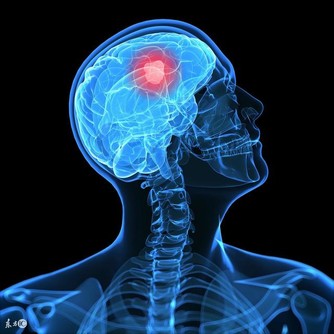

如果經常覺得胃口欠佳、無論睡多久都還是會不小心打瞌睡、平常很細嫩的皮膚起了紅疹子,那可能是體內的濕氣在作怪了! 數千年前中醫就提到氣候環境變化對身體產生的影響,其中「濕氣」是其中一項引發疾病和慢性病的關鍵因子。

正常情況下,我們人體對於外界溫度、濕度變化會有自然調節能力,但現代人因體質、飲食或生活習慣不正常,長年累積造成水分調控系統漸漸失衡,多餘的水分排不掉,久而久之會如同洪水潰堤,體內運作變差,甚至新陳代謝受阻。 先檢視妳的日常作息是不是很少運動、暴飲暴食、熬夜與精神壓力沉重,總是手腳冰冷,尤其換季季節的微病徵: